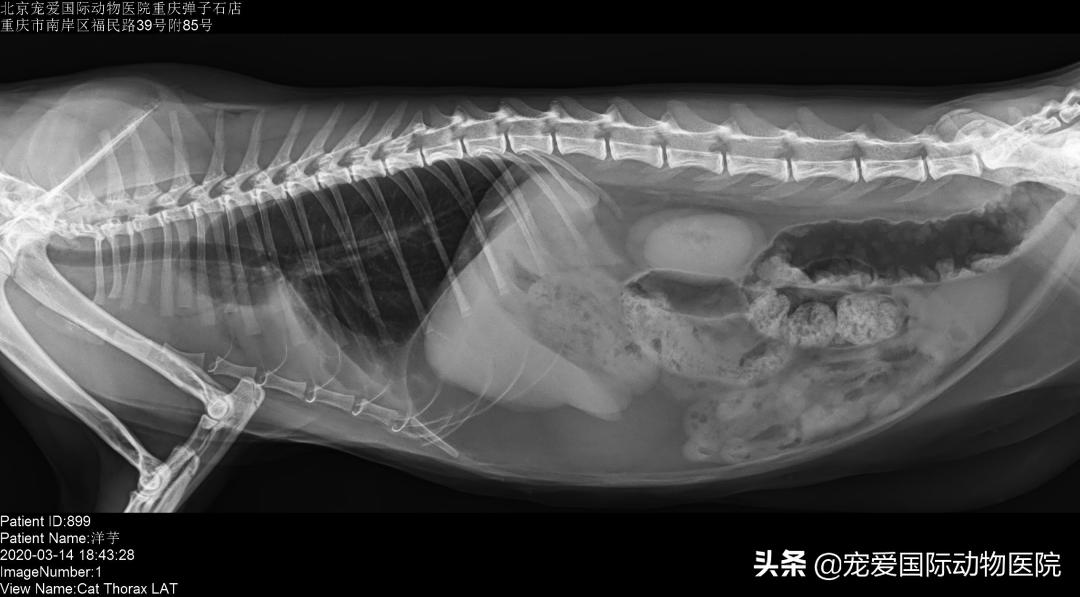

经过一周治疗,洋芋呼吸情况明显好转,食欲恢复正常,精神良好,排便情况正常,复查x光胸水逐步在减少,肺叶逐渐恢复正常。继续用药到3周复查,胸水消失,各项指标恢复正常。整体治疗效果良好,遂出院。

治疗第二周,胸水逐步减少,呼吸趋于平稳。

治疗第三周肺叶逐步恢复正常,胸水消失。